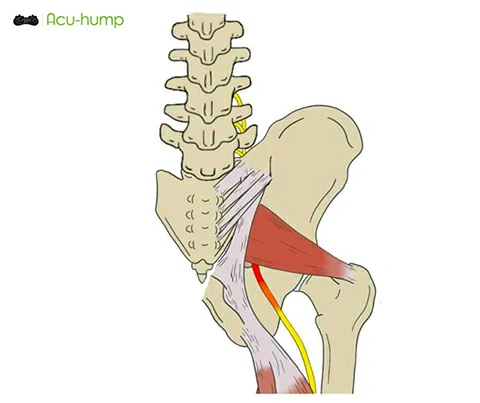

There are several common causes of piriformis syndrome. One of the primary causes is the tightening of the piriformis muscle, which can result from overuse or lack of stretching. Additionally, the piriformis muscle may become irritated or damaged, leading to the development of this condition.

Acu-hump is an incredibly effective tool for massaging and stretching the piriformis muscle. This muscle is located deep in the buttock area and can become tight and inflamed, leading to pain and discomfort. By incorporating Acu-hump into your daily routine, you can help to release tension in the piriformis muscle and promote overall relaxation in the lower body.

Using Acu-hump to massage the piriformis muscle is simple and effective. Simply place the tool under the affected area and use it to apply pressure to the muscle. You can adjust the pressure to your liking and focus on areas that feel particularly tight or painful. The raised bumps on the tool will work to target and release pressure in the muscle, promoting relaxation and pain relief.

In addition to massage, stretching with Acu-hump can also be incredibly effective for releasing tension in the piriformis muscle. By using the tool to support and extend the muscle, you can work to increase flexibility and reduce the likelihood of injury. Regular stretching exercises can help to prevent the development of piriformis syndrome, while also promoting overall health and well-being.